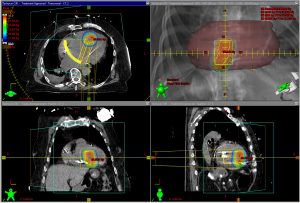

Erstmalig in Deutschland: Erfolgreiche Bestrahlungstherapie lebensbedrohlicher Herzrhythmusstörung10. Dezember 2018 Abb. 1: Mithilfe eines der weltweit modernsten Mappingsysteme wurde aus mehr als 10.000 Datenpunkten eine hochauflösende Darstellung der linken Herzkammer im elektrophysiologischen Labor erstellt, um so die Zielregion für die Bestrahlung zu identifizieren. Bild. © UKSH Als einer der ersten Patienten weltweit und als erster Patient in Deutschland konnte am 30. November 2018 ein 79-jähriger Mann mit lebensbedrohlichen und therapierefraktären Herzrhythmusstörungen mittels einer hochpräzisen einmaligen Bestrahlung erfolgreich behandelt werden. Die neuartige Behandlungsmethode wurde in enger Kooperation der Klinik für Innere Medizin III und der Klinik für Strahlentherapie am Universitätsklinikum Schleswig-Holstein (UKSH), Campus Kiel, durchgeführt. Der Patient leidet an einer schweren Herzmuskelerkrankung und erhielt trotz einer maximalen antiarrhythmischen medikamentösen Therapie von seinem implantierten Defibrillator fast täglich eine Schockabgabe. „Nach der erfolgreichen Bestrahlung sind die bösartigen Herzrhythmusstörungen bislang nicht wieder aufgetreten“, sagt Prof. Hendrik Bonnemeier, stellvertretender Klinikdirektor der Klinik für Innere Medizin III und Leiter der Abteilung für Elektrophysiologie und Rhythmologie. Gemeinsam mit dem Direktor der Klinik für Strahlentherapie, Prof. Jürgen Dunst, wurde dieser individuelle Heilversuch akribisch geplant und über ein halbes Jahr vorbereitet. „Die höchst innovative und zukunftsweisende Therapie ist ein sehr gutes Beispiel für die herausragende interdisziplinäre Kooperation am UKSH und zeigt das Potential universitärer Spitzenmedizin“, sagt Dunst. Zur Vorbereitung der Strahlenbehandlung erstellten Bonnemeier und OA Dr. Thomas Demming mittels eines der weltweit modernsten Mappingsysteme aus mehr als 10.000 Datenpunkten eine hochauflösende Darstellung der linken Herzkammer im elektrophysiologischen Labor, um so die Zielregion für die Bestrahlung zu identifizieren (s. Abb. 1). Abb. 2. Bild: © UKSH Anschließend wurde die gezielte Bestrahlung durch ein Team von Strahlentherapeuten und Medizinphysikexperten um OA Dr. David Krug und Prof. Dr. Frank-Andre Siebert geplant, berechnet und schließlich bei dem Patienten erfolgreich durchgeführt (Abb. 2). Die hochpräzise Bestrahlung zeigt eine neue, höchst innovative und möglicherweise wegweisende Therapieoption für bestimmte Patienten mit therapierefraktären ventrikulären Tachykardien auf. Eine prospektive Studie unter Leitung des UKSH Campus Kiel soll ab dem kommenden Jahr diese Methode bei betroffenen Patienten genauer untersuchen. Weitere Informationen: http://www.uksh.de/181207_pi_herzpatient_strahlenth.html